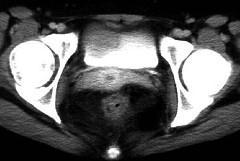

问题 女,32岁,腹痛、腹泻、便秘交替出现,粘液血便半年,里急后重,影像检查如图,最佳的诊断是 ( )

选项 A.结肠癌 B.慢性结肠炎 C.过敏性结肠炎 D.溃疡性结肠炎 E.肠结核

答案 D